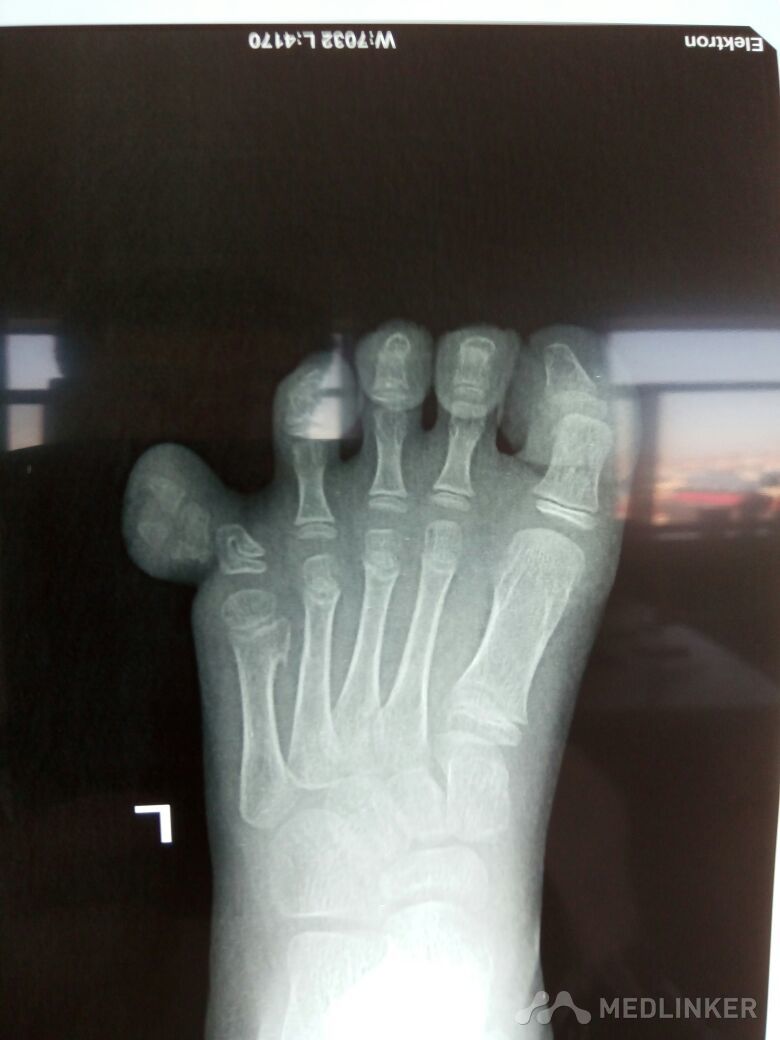

小儿多趾畸形一例

先天性足畸形

多趾畸形